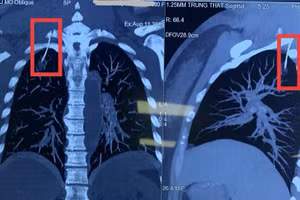

GD&TĐ - Một phụ nữ 45 tuổi ở Hà Nội nhập viện sau khi châm cứu tại phòng khám tư nhân, bác sĩ phát hiện kim châm xuyên vào màng phổi.